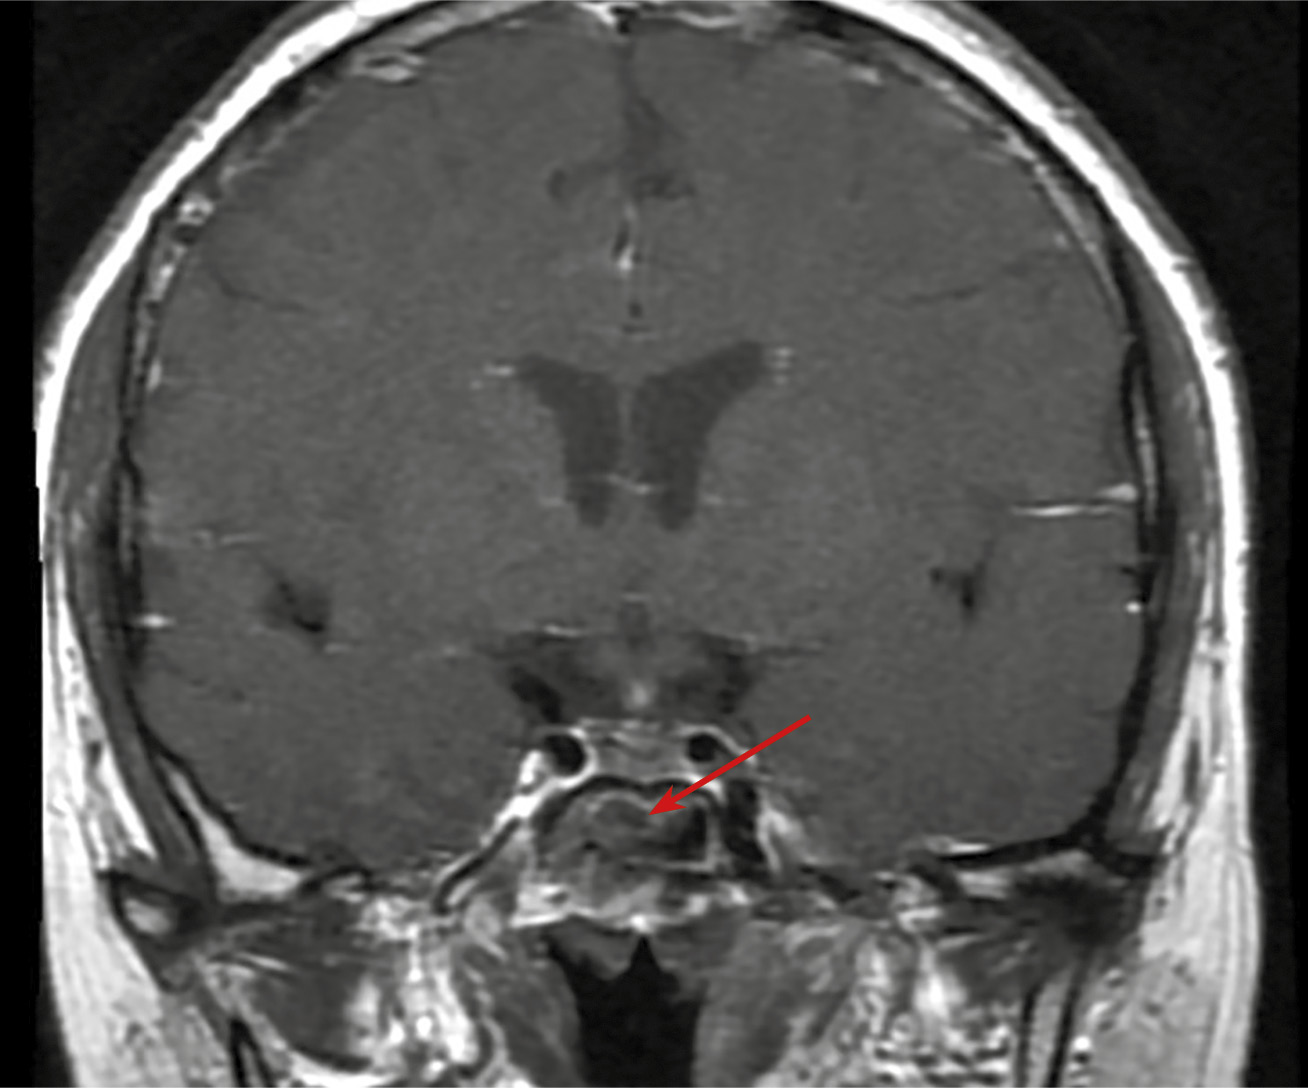

Пациент Г., мужчина 73 лет, отметил появление выраженных зрительных нарушений (снижение остроты зрения на левый глаза, двоение) с последующим ухудшением. Данная симптоматика возникла через 6 лет после радикальной левосторонней нефрэктомии в 2017 г., выполненной по поводу светлоклеточного почечноклеточного рака (рТ2N0M0). По данным компьютерной томографии через 4 года (2021 г.), выявлена опухоль в правой почке 14х15х14 мм солидной структуры. В январе 2022 г. в связи с потерей сознания госпитализирован в городскую больницу по месту жительства, где диагностирована вторичная надпочечниковая недостаточность. Назначена заместительная терапия препаратами преднизолона. Впервые в феврале 2022 г. выполнена КТ головного мозга, обнаружены признаки объемного образования хиазмально-селлярной области, пролабирующего через верхнюю апертуру турецкого седла с ровными контурами, размером 10х12х14 мм, параселлярные структуры без особенностей. МРТ не проводилась в связи с клаустрофобией у пациента. Во время госпитализации в ГНЦ ФГБУ НМИЦ эндокринологии в марте 2022 г. подтверждена вторичная надпочечниковая недостаточность (АКТГ <5,00 пг/мл (0–46), кортизол <1,00 мкг/дл (5–25), а также установлен гипогонадотропный гипогонадизм (тестостерон — 3,22 нг/дл (167–654), ФСГ — 0,32 мМЕ/мл (0,95—11,95). При обследовании была исключена гормональная активность опухоли при наличии умеренного повышения уровня общего пролактина до 1243 мЕд/л, что было интерпретировано как масс-эффект опухоли. По результатам МСКТ забрюшинного пространства с контрастным усилением, данных за рецидив заболевания не получено, сохраняется образование правой почки, без отрицательной динамики. При повторной госпитализации через 1 год (март 2023 г.) отмечалась отрицательная динамика в виде прогрессирования зрительных нарушений и роста образования хиазмально-селлярной области до 18х27х15 мм с признаками сдавления хиазмы и пролабирования в полость 3 желудочка на 7,2 мм, компримируя его передние отделы (рис. 3.1).

Пациент осмотрен офтальмологом, выполнена компьютерная периметрия, выявлено сужение периферической границы поля зрения концентрическое на 10 градусов справа, с височной стороны на 15–20 градусов слева. При обследовании данных за наличие метастазов почечноклеточного рака другой локализации не получено.

Рисунок 3.1. КТ головного мозга.